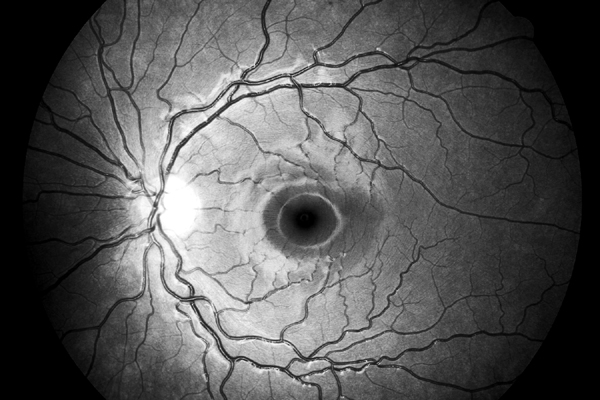

Vrstva nervových vláken

Oftalmo-neurologická diagnostika 1956, Michelem popsaný obraz si můžeme kdykoliv vyvolat, vyšetřujeme-li oční pozadí podle Vogtova návrhu bezčerveným světlem.

The temporal raphe of the human retina Amer.J.ophthal. 62:926/1966, popsal předěl ve vrstvě nervových vláken temporálně od makuly mezi horní a dolní polovinou sítnice.